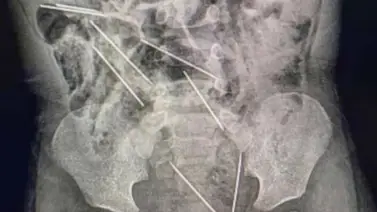

Los médicos le realizaron los estudios en los que detectaron la presencia de las agujas diversas partes de su cuerpo: dos en el peritoneo lado derecho, tres en el lado izquierdo, uno en la pared abdominal y las dos restantes entre la vejiga y el recto.